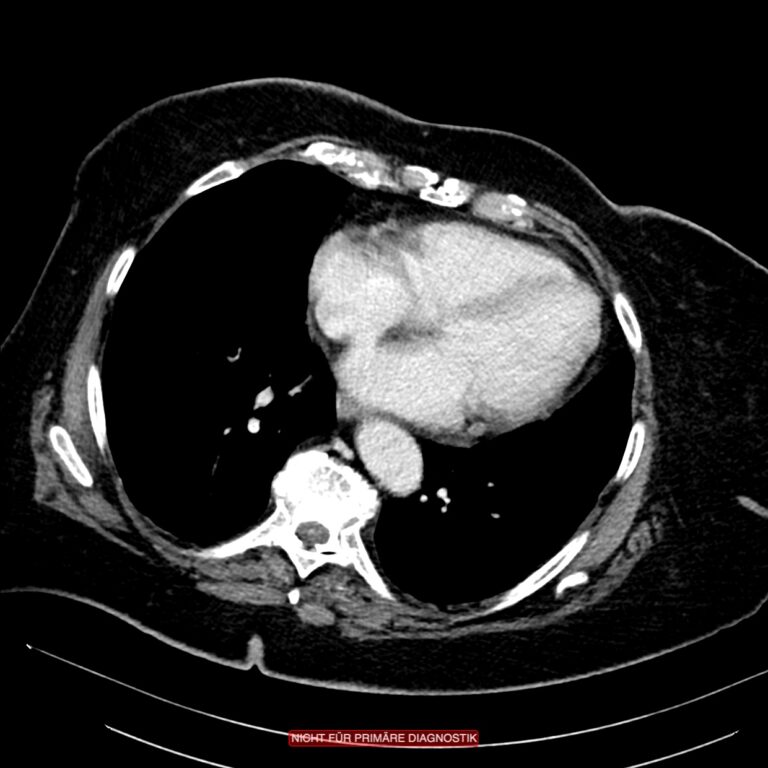

Die weitere Diagnostik, die zuverlässig hilft, den Schwergrad der Erkrankung einzuschätzen, ist die Computertomografie des Abdomens mit rektaler Kontrasmittelfüllung. Früher wurde oft ein Kolon-Kontrasmitteleinlauf zur Diagnostik eingesetzt. Mit dieser für diese Fragestellung heute obsoleten Untersuchungsmethode ließen sich zwar sehr schön die Divertikel darstellen, nicht aber das Geschehen außerhalb des Darmes. Da die akute Divertikulitis in ihrer Schwere aber durch die extraluminale Entzündungsreaktionen bestimmt wird, also durch die Peridivertikulitis, ist der Kolon-KE als diagnostisches Mittel hier unwirksam, weil der extraluminäre Teil der Entzündung nicht abgebildet werden kann.